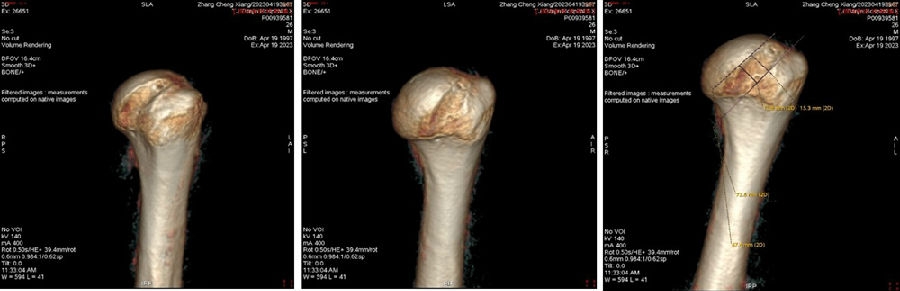

双侧CT三维扫描显示:健侧肩胛盂宽度D=25.9,患侧D=23.9,患侧肩胛盂骨性缺损d=6.2,骨性盂唇缺损面积d/D为23.9%(<25%)。肩胛盂轨迹GT(83%D-d)为15.3mm。

图28双侧CT三维扫描

图29 Hill-Sachs间隙为13.8mm(<15.3mm)

图30 评估结果

评估报告提示:右肩胛骨关节盂前下缘撕脱骨折,符合骨性bankart损伤。右肱骨头后上缘凹陷骨折,符合Hill-Sachs损伤。Hill-Sachs间隙为13.8mm(<15.3mm),为轨迹内肩关节前脱位。